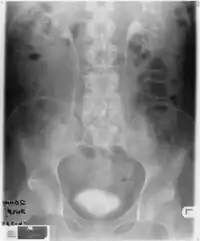

Infection of Brindley sacral anterior root stimulator-End of S-4 cable showed scanty growth of Klebsiella aerogenes (and Pseudomonas aeruginos)Intravenous urography, which was performed, showed excretion of contrast by both kidneys.